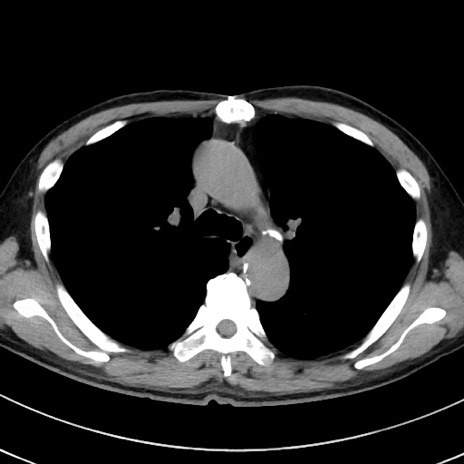

症例38(横断像)

【症例】70歳代 男性

【主訴】腹痛・嘔吐

【現病歴】昨晩より、嘔吐・腹痛あり。今朝になっても嘔吐あり。来院。

【既往歴】心臓バイパス手術、開腹胆摘、腸閉塞

【身体所見】BP 107/71mmHg、HR 116/min、腹部:平坦、軟、下腹部に軽度圧痛あり。反跳痛なし。

【データ】WBC 15100、CRP 0.32